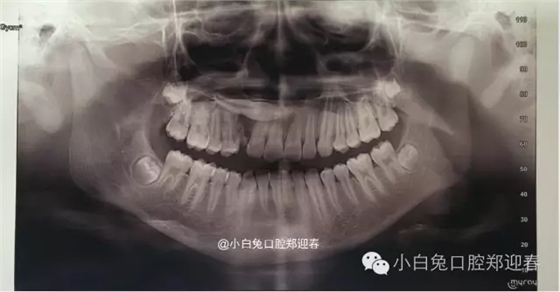

術(shù)前全景片

全景片顯示:53滯留,13橫位阻生,但是全景片反映不出真實(shí)的阻生尖牙的解剖位置,因此要借助CT進(jìn)行定位。